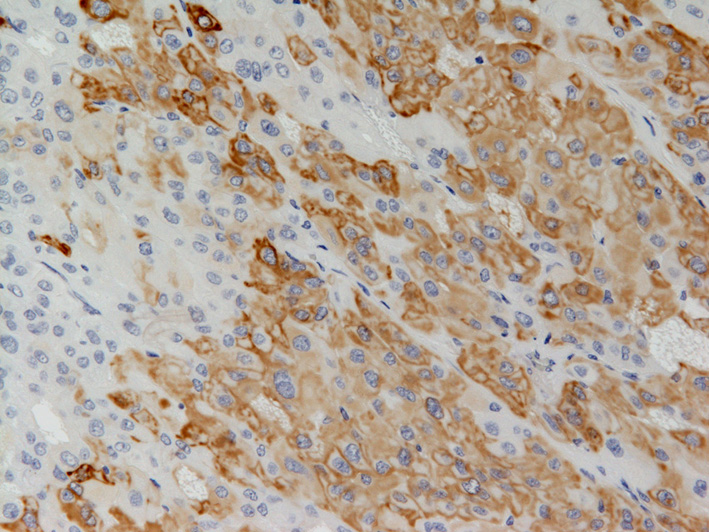

| CK7の免疫染色(対物x20).腫瘍細胞の多くは陽性であるが,所々で陰性細胞集塊を混在する. |